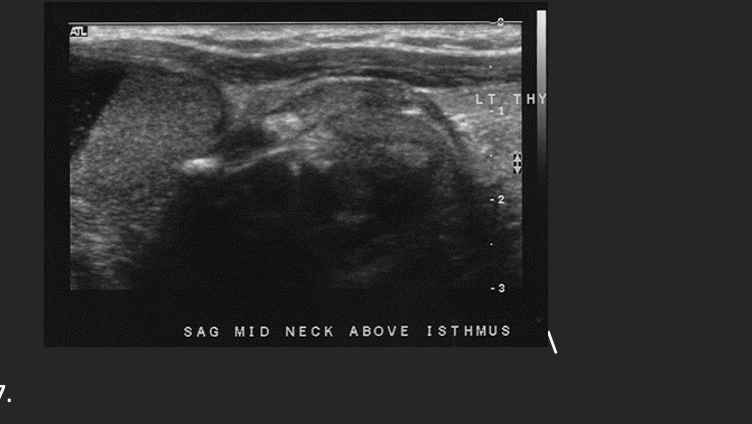

A patient presents with a palpable anterior neck mass. The patient denies any recent surgery or fever. A nonvascular complex mass is identified extending from the superior portion of the isthmus to the patients chin. On the basis of this clinical history, the sonographic findings are most suspicious for:

C. Thyroglossal cyst